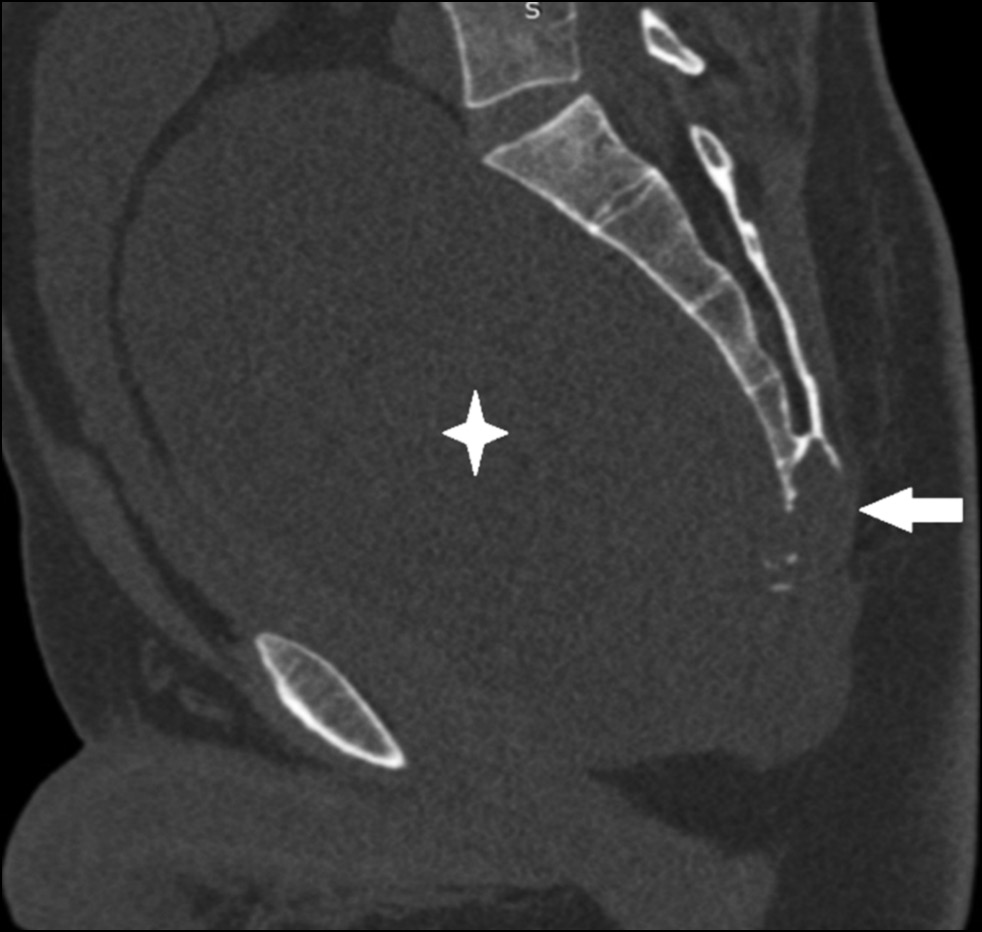

Computed tomography (CT) of the pelvis (Fig. 3) revealed a focus of lithic destruction in the S4, S5, and coccygeal vertebrae without clear contours. The destruction extended into the surrounding soft tissues and spread to the distal part of the sacral canal up to the level of the S4 vertebrae. A massive soft tissue component of the tumor, measuring up to 200 mm in length, was visualized on the anterior surface of the sacrum, reaching the level of the L5 vertebra. The tumor had clear contours on the side of the small pelvis and abdominal cavity, and it compressed and displaced the bladder and rectum. CT of the chest revealed no focal or infiltrative changes in the lungs.

Fig. 3. CT in the sagittal plane, there is a lytic focus of destruction of the C4, C5 and coccygeal vertebrae (arrow), a massive soft tissue component in the pelvic cavity, reaching the level of the L5 vertebra (asterisk).